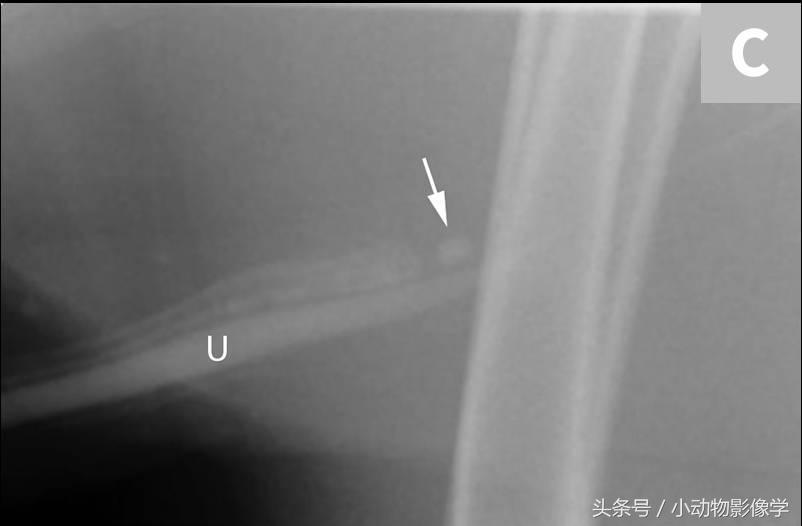

阴茎骨相关的成骨作用的单独中心可能会与尿道结石十分相似(图11A和B)。骨化中心可以出现在阴茎骨的任意一端,且与阴茎骨在同一直线上。尿道海绵体内的结石位于阴茎骨腹侧的尿道部位。对比尿道造影在区分尿道结石和分离的骨化中心会非常有用(图11C)。

图11A、一只公犬的侧位平片,包括膀胱和阴茎骨。注意接近并与阴茎骨根部处于在同一水平的界限清楚不透明矿化区域,这是一个单独的骨化中心(箭头)。包皮上两个不透明软组织结节推测为小乳头(三角箭头)。

图11C、图11A的犬的利用荧光镜的阳性对比尿道造影术。注意不透明矿化区域下方是充满了碘化造影剂的尿道(U),确认为单独的骨化中心(箭头),不要与尿道结石弄混。